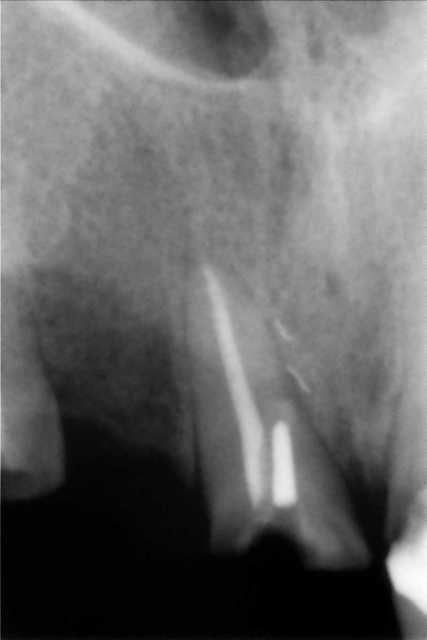

devant cette fracture de tenon desaxé sur 11;absence de signe clinique;supraclusion +++:

essai de conservation de la dent en tentant de retirer le tenon ou en passant à coté ?

extraction ?

en fait il a deja un bridge 3 elements 13.12.11 remplaçant 12